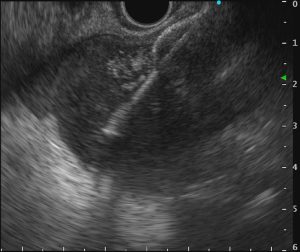

重症急性膵炎後のWONに対するEUS下膿瘍ドレナージ

肝門部胆管癌に対するEUS下胆道ドレナージ

急性胆嚢炎に対するEUS下胆嚢ドレナージ(LAMS留置)